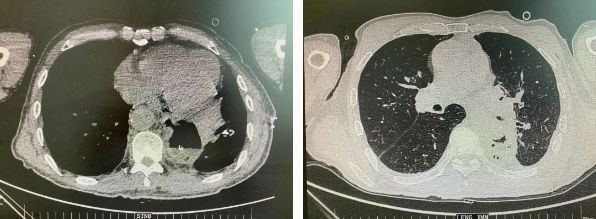

近日,胸科醫(yī)院執(zhí)行院長(zhǎng)李小飛教授帶領(lǐng)胸外科一病區(qū)團(tuán)隊(duì)完成一臺(tái)復(fù)雜胸外科手術(shù):食管癌與肺癌同期手術(shù)。

患者王某不幸同時(shí)患食管癌與左肺癌,病理類型系雙源發(fā)腫瘤,食管為鱗癌、肺為腺癌。食管癌和肺癌為胸外科最常見的疾病,但同時(shí)患兩種疾病,十分罕見。家屬輾轉(zhuǎn)多個(gè)醫(yī)院,得知李小飛院長(zhǎng)擅長(zhǎng)胸外科復(fù)雜手術(shù),慕名來西安國(guó)際醫(yī)學(xué)中心醫(yī)院。

經(jīng)過李小飛教授、李文海副教授、穆強(qiáng)副主任醫(yī)師團(tuán)隊(duì)積極準(zhǔn)備,排除手術(shù)禁忌;經(jīng)過全科術(shù)前充分討論,大家認(rèn)為:如果分兩次進(jìn)行手術(shù),另一種疾病勢(shì)必會(huì)受到影響,腫瘤可能進(jìn)展。胸外科手術(shù)對(duì)呼吸循環(huán)影響較大,同期實(shí)施兩個(gè)手術(shù)更要小心謹(jǐn)慎。李小飛教授主持術(shù)前討論,設(shè)計(jì)合理手術(shù)方式,由于食管癌胸腔鏡手術(shù)為右側(cè)入路,但為兼顧左肺癌手術(shù),則采用傳統(tǒng)左開胸手術(shù)。

2022年4月25日,由李小飛教授主刀,同期行左側(cè)開胸:食管癌根治術(shù) 左肺癌根治術(shù),一次手術(shù)同時(shí)根治兩種惡性腫瘤疾病。經(jīng)過精細(xì)手術(shù)及術(shù)后管理,患者術(shù)后十天,恢復(fù)良好,進(jìn)食良好,現(xiàn)已出院。